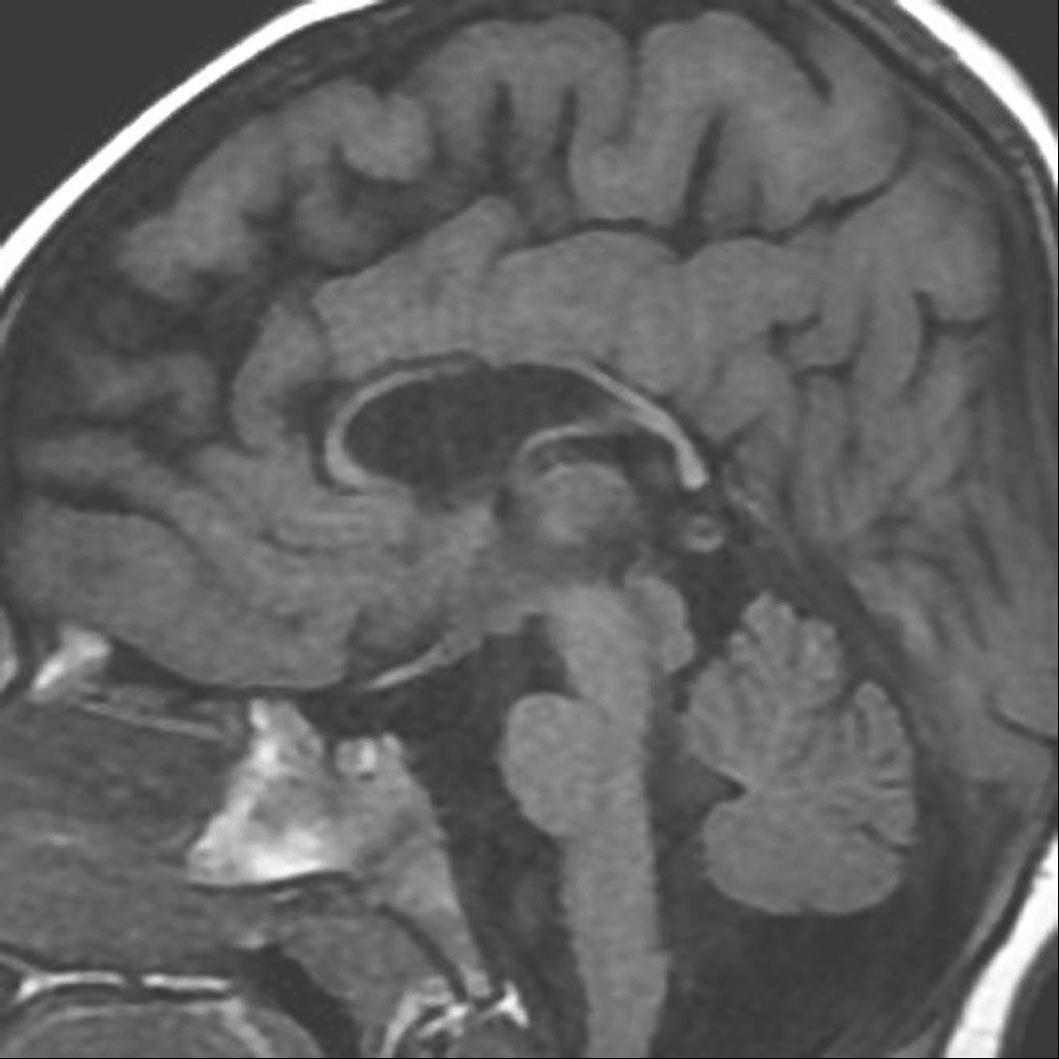

图2-3-1 孕22周胎儿头颅MRI平扫

A.矢状位T 2 WI,胎儿胼胝体未见显示;B.冠状位T 2 WI示双侧侧脑室分离呈“公牛角”样改变